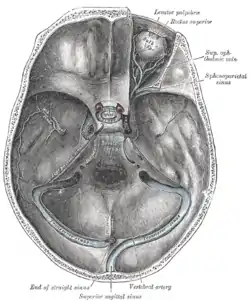

The sinuses at the base of the skull. (Sphenoparietal sinus labeled at upper right.) | |

The sphenoparietal sinus is a paired dural venous sinus situated along the posterior edge of the lesser wing of either sphenoid bone. It drains into the cavernous sinus.[2]

A sphenoparietal sinus is situated under each lesser wing of the sphenoid bone near the posterior edge of this bone,[2] between the anterior cranial fossa and middle cranial fossa. It terminates by draining into the anterior part of the cavernous sinus.[2]

A sphenoparietal sinus receives small veins from the adjacent dura and sometimes the frontal ramus of the middle meningeal vein, communicating rami from the superficial middle cerebral vein, temporal lobe veins, and the anterior temporal diploic veins.[2]